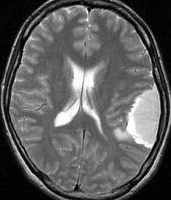

この髄膜腫は中程度の大きさのものです。円蓋部髄膜種という最も多い最も手術の簡単なタイプです。麻痺や失語症やてんかんなどの症状はありません。とても美しくて若い女性の髄膜腫でしたが,子供に遺伝はしませんし,癌などと違ってタバコなどこれといった原因がなくて発生するものです。

MRIでの髄膜腫の見え方は撮影の仕方によっていろいろです。左からT1強調画像,T2強調画像,フレア画像といいます。腫瘍の横に小さく白い領域がありますが,これは脳の腫れた部分で脳浮腫といいます。髄膜腫があると周囲に脳浮腫が生じることがあります。